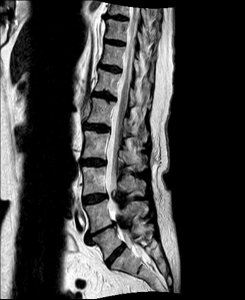

MRI with lateral reconstruction of the lumbar spine. The hourglass-like narrowing of the spinal canal can be seen at two heights.